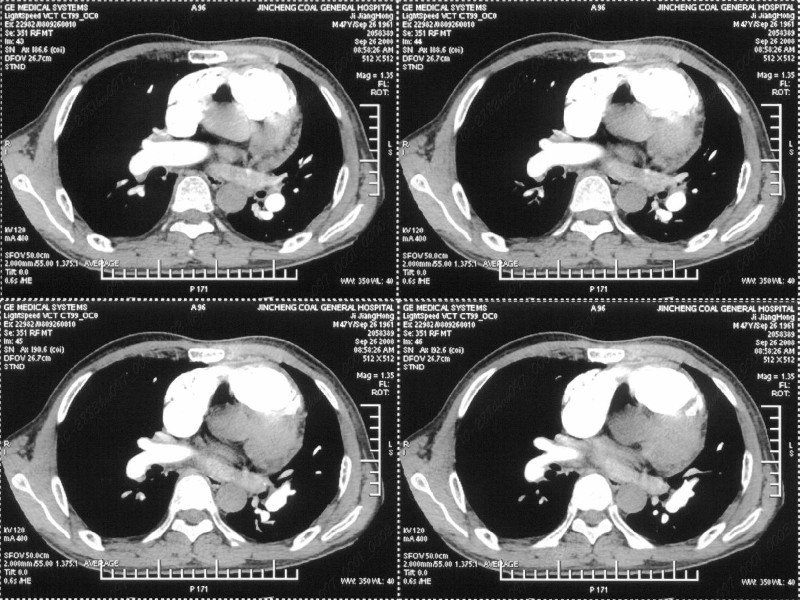

男性,47岁。胸部不适一年,ct检查发现右胸膜下结节。http://www.radida.com/bbs/forum.php?mod=viewthread&tid=46094

图像很清,资料很全。工作做的很细,向您学习!观阁下的强化图像发现,您们强化后扫描时间挺早,延迟时间大约在16—18秒之间吧。估计目的是为了观察肺动脉及分支的情况。但现有的资料并不能提示动脉栓塞改变。建议楼主可在机器上仔细观察,或许会有异常发现。另外,个人感觉右侧应为肺内结节而非胸膜结节。考虑肺内良性小结节,炎性假瘤可能性大。

病灶周围似有纤维化征像,增强明显强化,但中央可见点状低强化区,考虑慢性病变可能如炎性假瘤等,病灶边缘部分毛糙有切迹,双侧胸腔少量积液影,不除外恶性

结节未见明显强化,局部胸膜增后粘连,内缘纹理影增重伴小围星灶,局部胸膜下小三角状实变影,尖端见纤维索牵扯征,综合考虑炎性病变,有增殖表现,不出外tb灶

右肺中叶外侧段胸膜下结节状病灶,性质待定(不排除周围型肺癌可能)。

汇报临床诊断:右肺动脉分枝栓塞

右肺静脉充盈缺损,左心房体积小,右肺动脉远端动脉充盈缺损,右肺血管影细小,考虑;右肺动脉远端栓塞.